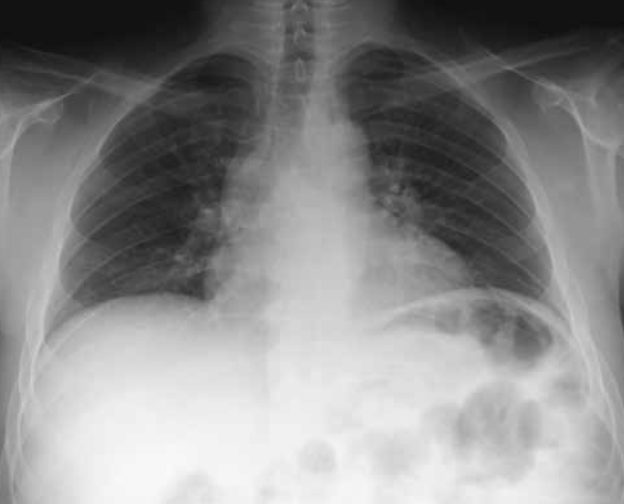

Imagen de TC de alta resolución que muestra fibrosis pulmonar.

Principales utilidades de TC de alta resolución son:

• Valorar el grado de afectación de enfermedades intersticiales pulmonares.

• En pacientes EPOC, para valorar el grado de enfisema y pequeñas zonas de atrapamiento aéreo.

• Determinar la gravedad y extensión de bronquiectasias.

• Valorar qué área es más rentable biopsiar.